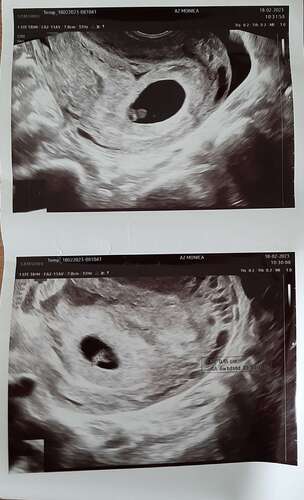

Ja hoor, en nu 21 weken zwanger. Niet te bang laten maken. Dit heet een hematoom en komt veel vaker voor dan je denkt.

Ja ik had mijn eerste echo gekregen vanwege bloedverlies met 5+3 en daar was toen een kloppend hartje te zien. Maar bij heel veel vrouwen lost dit vanzelf op😊

Dan zou ik proberen (makkelijker gezegd dan gedaan hoor, dat snap ik) me even geen zorgen te maken nu. Zodra je bloed ziet, zou ik wel direct aan de bel trekken. Omdat het nu nog zo klein is, zou het vruchtje bij een evt bloeding 'meegesleurd' kunnen worden nl...

Maarrrr; grote kans dat het vanzelf oplost! Je volgende echo is nu de termijn dan denk ik? Bij mij was het toen weg. Inmiddels bijna 16wk.